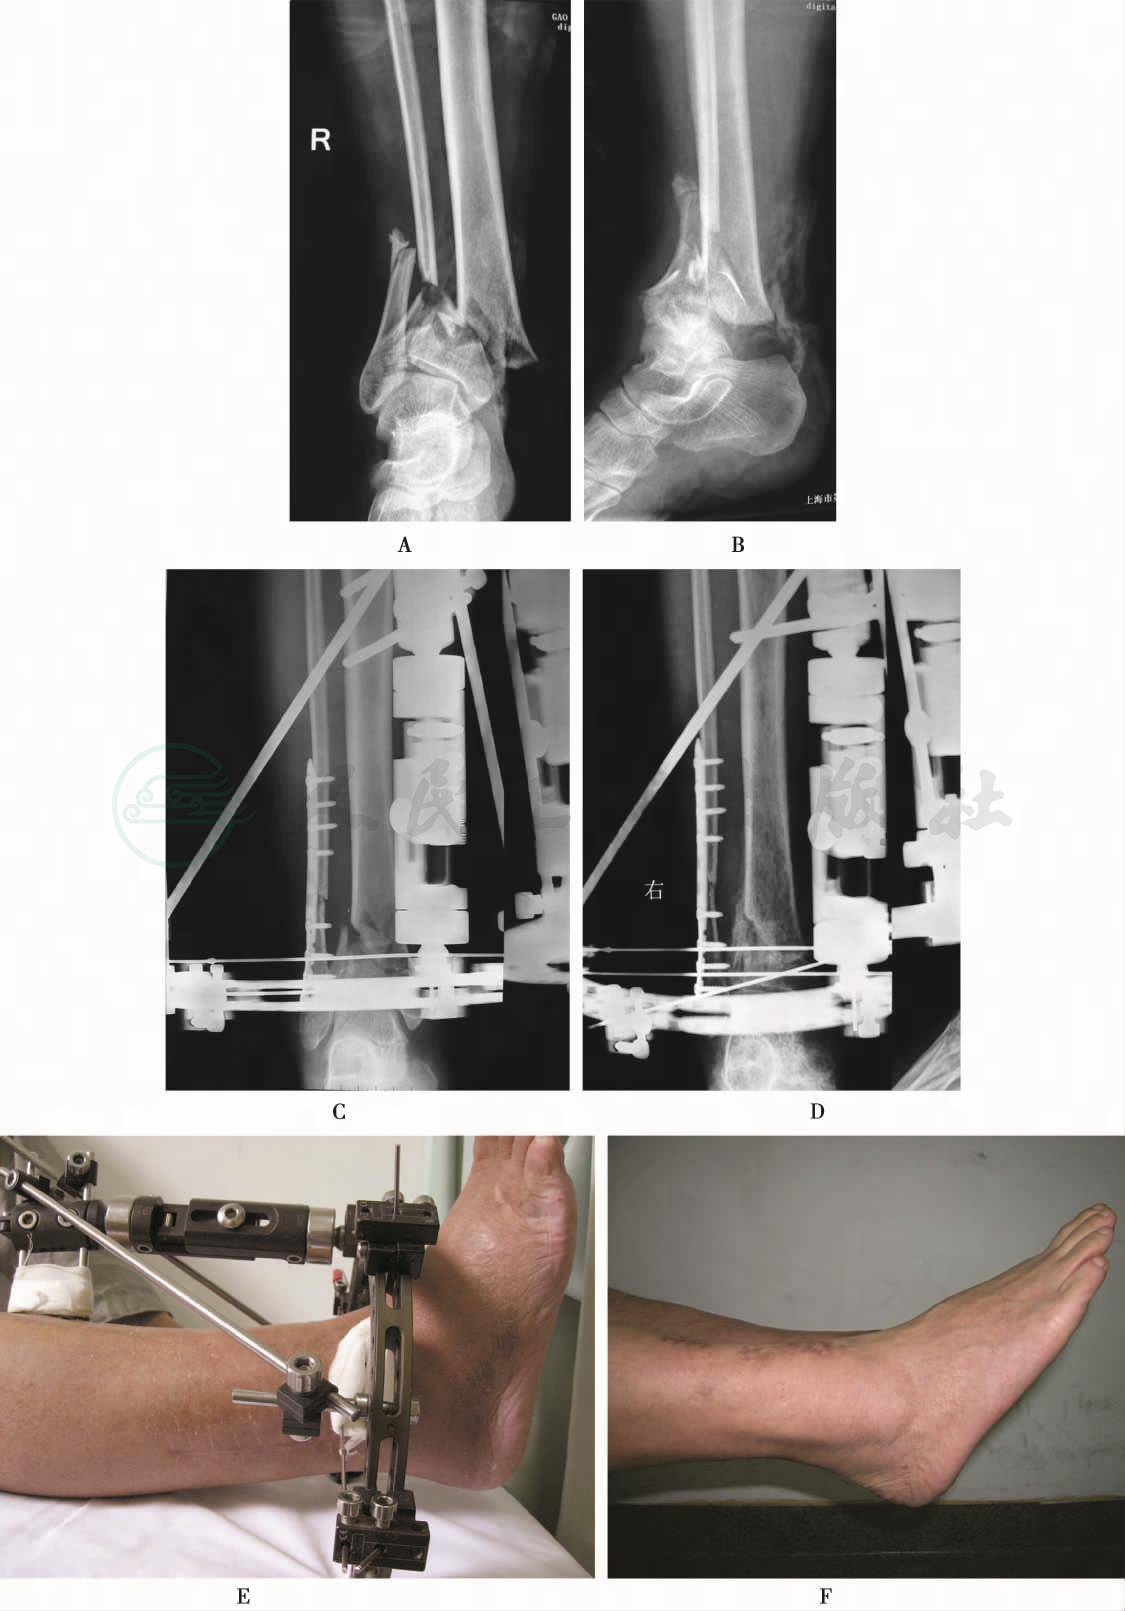

双侧踝关节正、侧位X线片和CT平扫片显示:双侧胫骨远端干骺端粉碎骨折伴移位,胫骨远端关节面受到累及出现骨折(图1)。心电图未见明显异常。血管B超显示双侧胫前、后血管及足背动脉血流充盈连续,无缺损,未见血栓形成。

图1 影像学检查

A、B、C.患者左侧踝关节正侧位X线片和CT片;D、E、F.右侧踝关节正侧位X线片和CT片